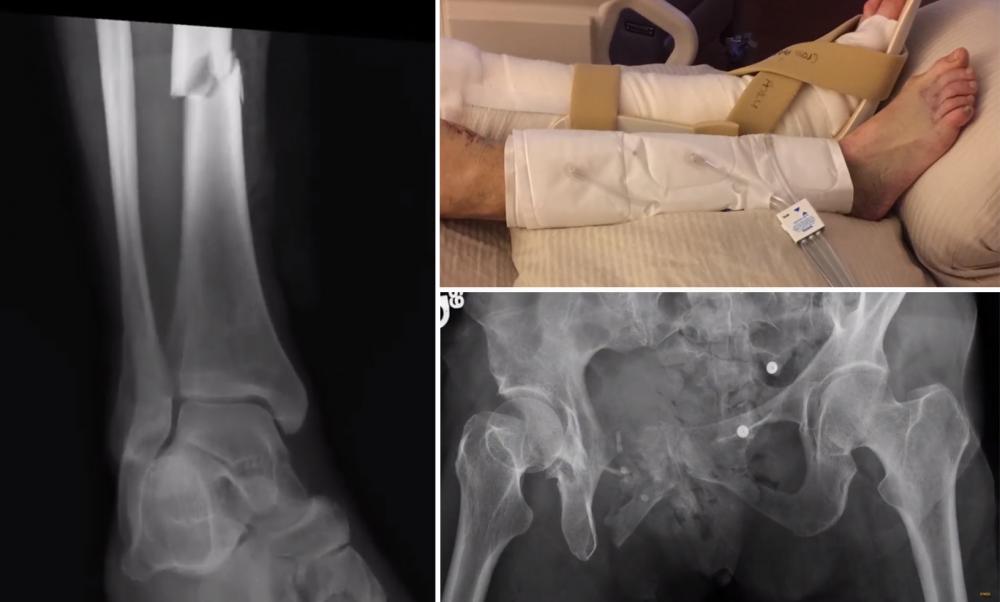

On the left and bottom, X-ray images show the broken leg and pelvis that Joyce Johnson suffered after being thrown from a bike trolley in 2015. On the top, a photo shows Joyce’s legs as she heeled at VCU Medical Center. Photos courtesy of the Johnsons

On the left and bottom, X-ray images show the broken leg and pelvis that Joyce Johnson suffered after being thrown from a bike trolley in 2015. On the top, a photo shows Joyce’s legs as she healed at VCU Medical Center. Photos courtesy of the Johnsons

The surgeon explained that Joyce had suffered broken bones in about 27 places, including her pelvis, leg, sacrum and ribs. She also needed a skin graft for lacerations on her leg. She had lost nearly half of the blood in her body by the time she arrived at VCU Medical Center, and likely had less than 20 minutes to live at that time if the bleeding had continued.

The surgeon told Rich that VCU Health teams were planning the first of what would eventually be nine surgeries, which included implanting a rod in Joyce’s leg, screwing three pieces of her delicate and nerve-filled sacrum back together, and reconstructing her pelvis.